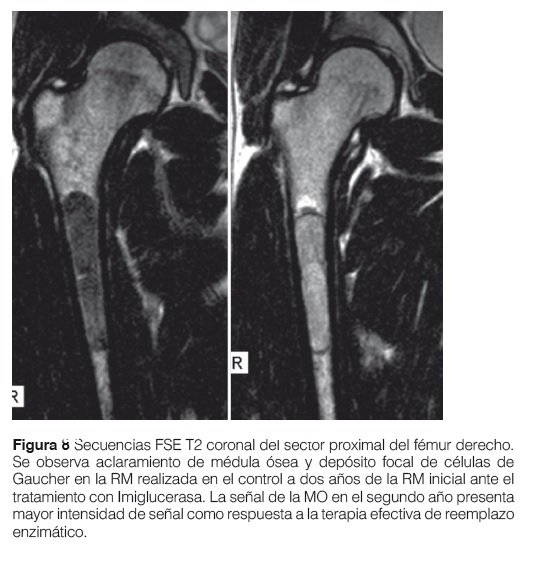

La evaluación de la enfermedad ósea es necesaria tanto al diagnóstico como en el seguimiento del paciente por lo menos una vez al año o frente a sintomatología aguda (dolor óseo-crisis óseo)9,10 (Fig. 7 y 8).